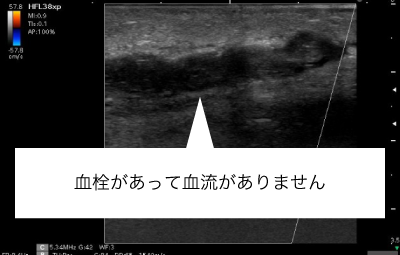

シャント血管が詰まってしまったとき(閉塞)などは、血栓を吸引するカテーテルをシャント血管内に挿入し、血栓を吸い取ります。

症例によりますが、シャント閉塞しても90%以上の患者さまは閉塞後7日間以内であればシャントを復活させることができます。